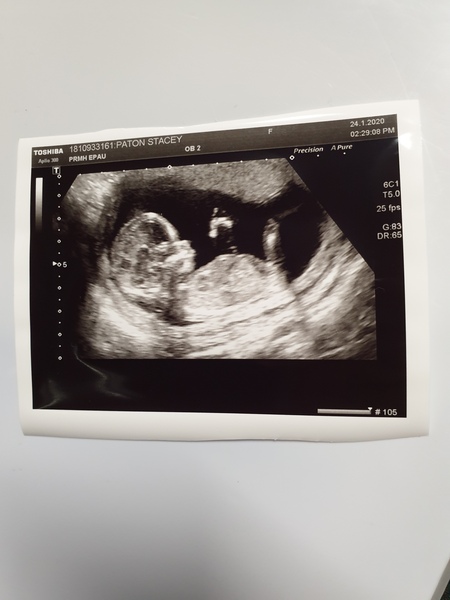

JackGordonsMummy · 24/01/2020 15:05

A very healthy little 14 week old ❤ says the bleeding was maybe from the placenta moving out from the pelvis that happens around this time. Baby was wriggling away.

@JackGordonsMummy fab news! What a lovely scan picture as well!

@JackGordonsMummy what a fab scan!! Congratulations again!